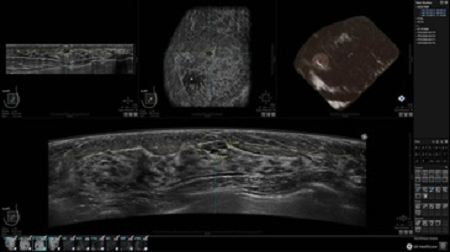

GE INVENIA ABUS – это современный УЗИ аппарат, который создан для точной и эффективной диагностики сканирования с высокой плотностью молочных желез. Выявляемость патологий раковых и предраковых стадий заболевания составляет 55%, что в конечном счете позволяет ставить врачу точные и своевременные диагнозы. Традиционные методы использования маммографии не показывают такой выявляемости, ограничиваясь лишь 3-38%.

УЗИ-аппарат GE INVENIA ABUS позволяет проводить максимально операторонезависимые процедуры, что значительно снижает риск неправильной постановки диагноза и сопутствующие издержки на обработку информации. Система готовит отчет в течение 3-х минут после сканирования, это безусловное преимущество по сравнению с обычным УЗИ сканером.

• датчик с изогнутой апертурой для качественного исследования

• сканирование одной грудной железы в трех проекциях не более 60 сек.;

• обработка результатов за три минуты.

Данное устройство классифицируется, как стационарное, используемое в многопрофильных клиниках, женских консультациях, медицинских центрах. Вес без учета дополнительного оборудования составляет 105 кг. Удобная колесная база позволяет оперативно маневрировать в ограниченных пространствах, в том числе передвигать устройство в коридорах клиники. Большой 17-ти дюймовый монитор с широкими углами обзора выводит максимально качественную картинку в формате Full HD.

Возможности встроенной УЗ-системы:

• Увеличение или уменьшение степени сжатия грудной железы;

• Функция автоматического сканирования активируется одним нажатием;

• Возможность отмены сканирования;

• Глубина проникновения УЗ-лучей – до 50 мм;

• Одно детализированное изображение можно получить менее чем за 1 минуту

• Многорядная светодиодная подсветка;

• Встроенный сверхширокий вогнутый датчик С15-6ХW.